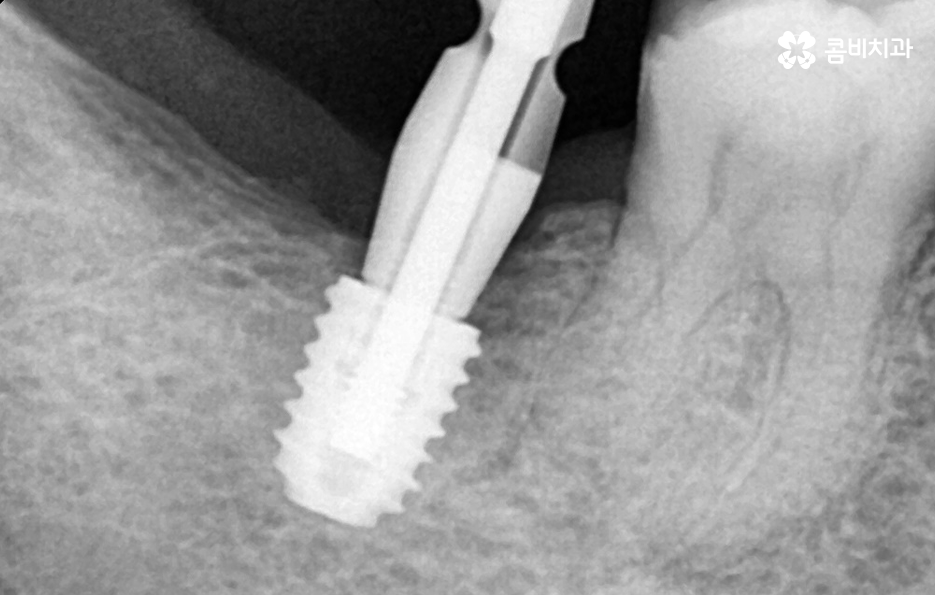

임플란트 치료의 성공 여부는 임플란트가 잇몸 뼈에 안정적으로 골유착이 진행되고 튼튼하게 고정되어 있어야 하기 때문에 치료 전에도 잇몸 건강이 중요하지만 치료 후에도 잇몸 건강이 관건이라 할 수 있는데요

어금니 임플란트 치료를 잘 받았다면 그 이후에는 얼마나 수명 유지를 잘하는지에 따라서 10년이상 건강하게 사용할 수도 있고 반대로 제대로 관리하지 않는다면 임플란트의 수명도 줄어들고 임플란트 주위염 등으로 고생하는 사례도 많이 있어요

임플란트는 한 번 치료 받으면 끝이 아니라 잘 관리하면 반영구적인 수명 유지도 가능하다는 사실을 기억하시고 오래 믿고 찾을 치과의 선택도 신중해야 하며 특히 노인 분들이나 전신질환이 있고 잇몸이 약한 분들이라면 임플란트 치료에 있어서 풍부한 임상 경험을 가진 치과의사와 충분히 상의하시고 1:1 맞춤 치료 계획을 잘 세우시길 권하고 있어요